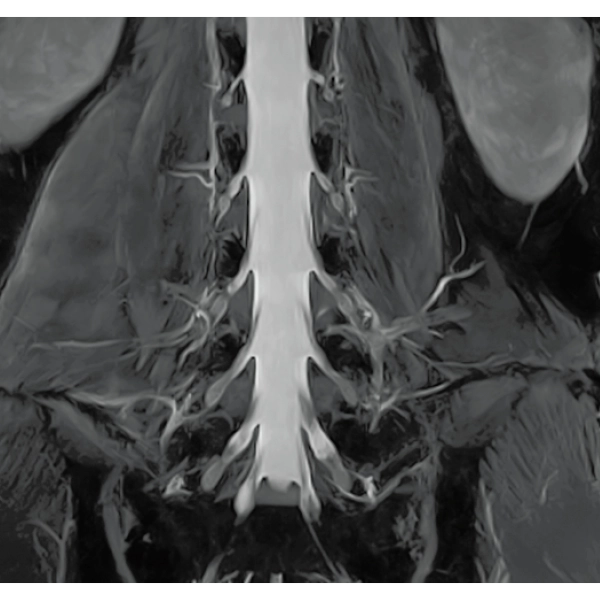

IP-RAPID x DLR Plus can be used for basic imaging such as VolumeScan, RadialScan, HalfScan, and many other imaging methods such as MultiContrastScan FatSep and DWI.

It can also be used with time-consuming scans such as Whole Body DWI and Whole Spine imaging, providing more detailed information in many areas than previously possible.